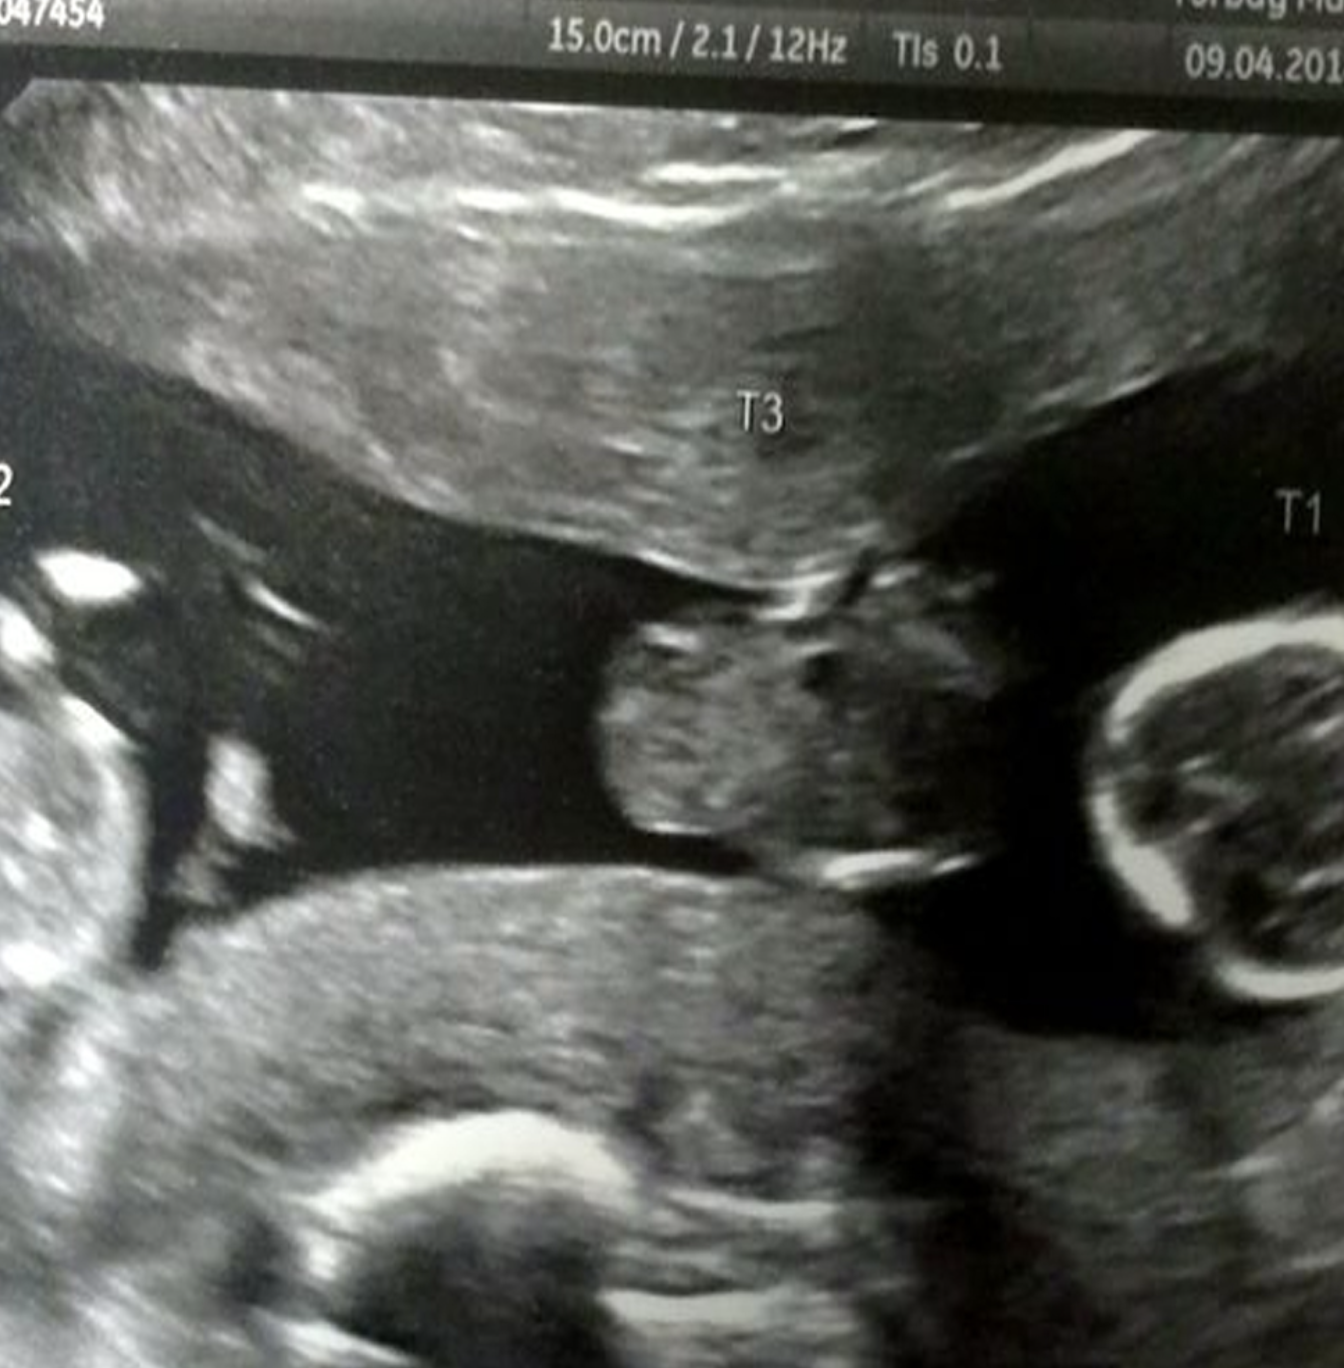

Melanie said: “I really disliked being pregnant the first time so I thought that was that. I was complete with daughter Tia, 13 but a couple of years ago my husband said he wanted to have another baby. He managed to talk me into it and I had my implant removed and we were pregnant after about four months.” Mother’s instinct told Melanie she might be carrying more than one baby, but a private scan at five weeks reassured her, after it appeared to show a single embryo. When they went for the 12 week scan at Torbay hospital, medics – who thought the couple must have had it – told the shocked pair they were expecting three.

Melanie said: “I kept having a recurring dream where the sonographer said to me ‘Have you had ? Have you got a history of twins in your family?’ So when we went for the 12 week scan and he said we were having triplets I thought it was a joke. Before the scan I had been saying something felt really different this time round. I said a few times ‘I’m sure there’s more than one’ but I never said anything about triplets. I just burst out laughing and asked ‘where are the cameras?’ I thought it must have been a joke, a set up.” Doctors warned the family of the dangers of multiple births and for the whole pregnancy they said the smallest baby – named Hope – was unlikely to survive.